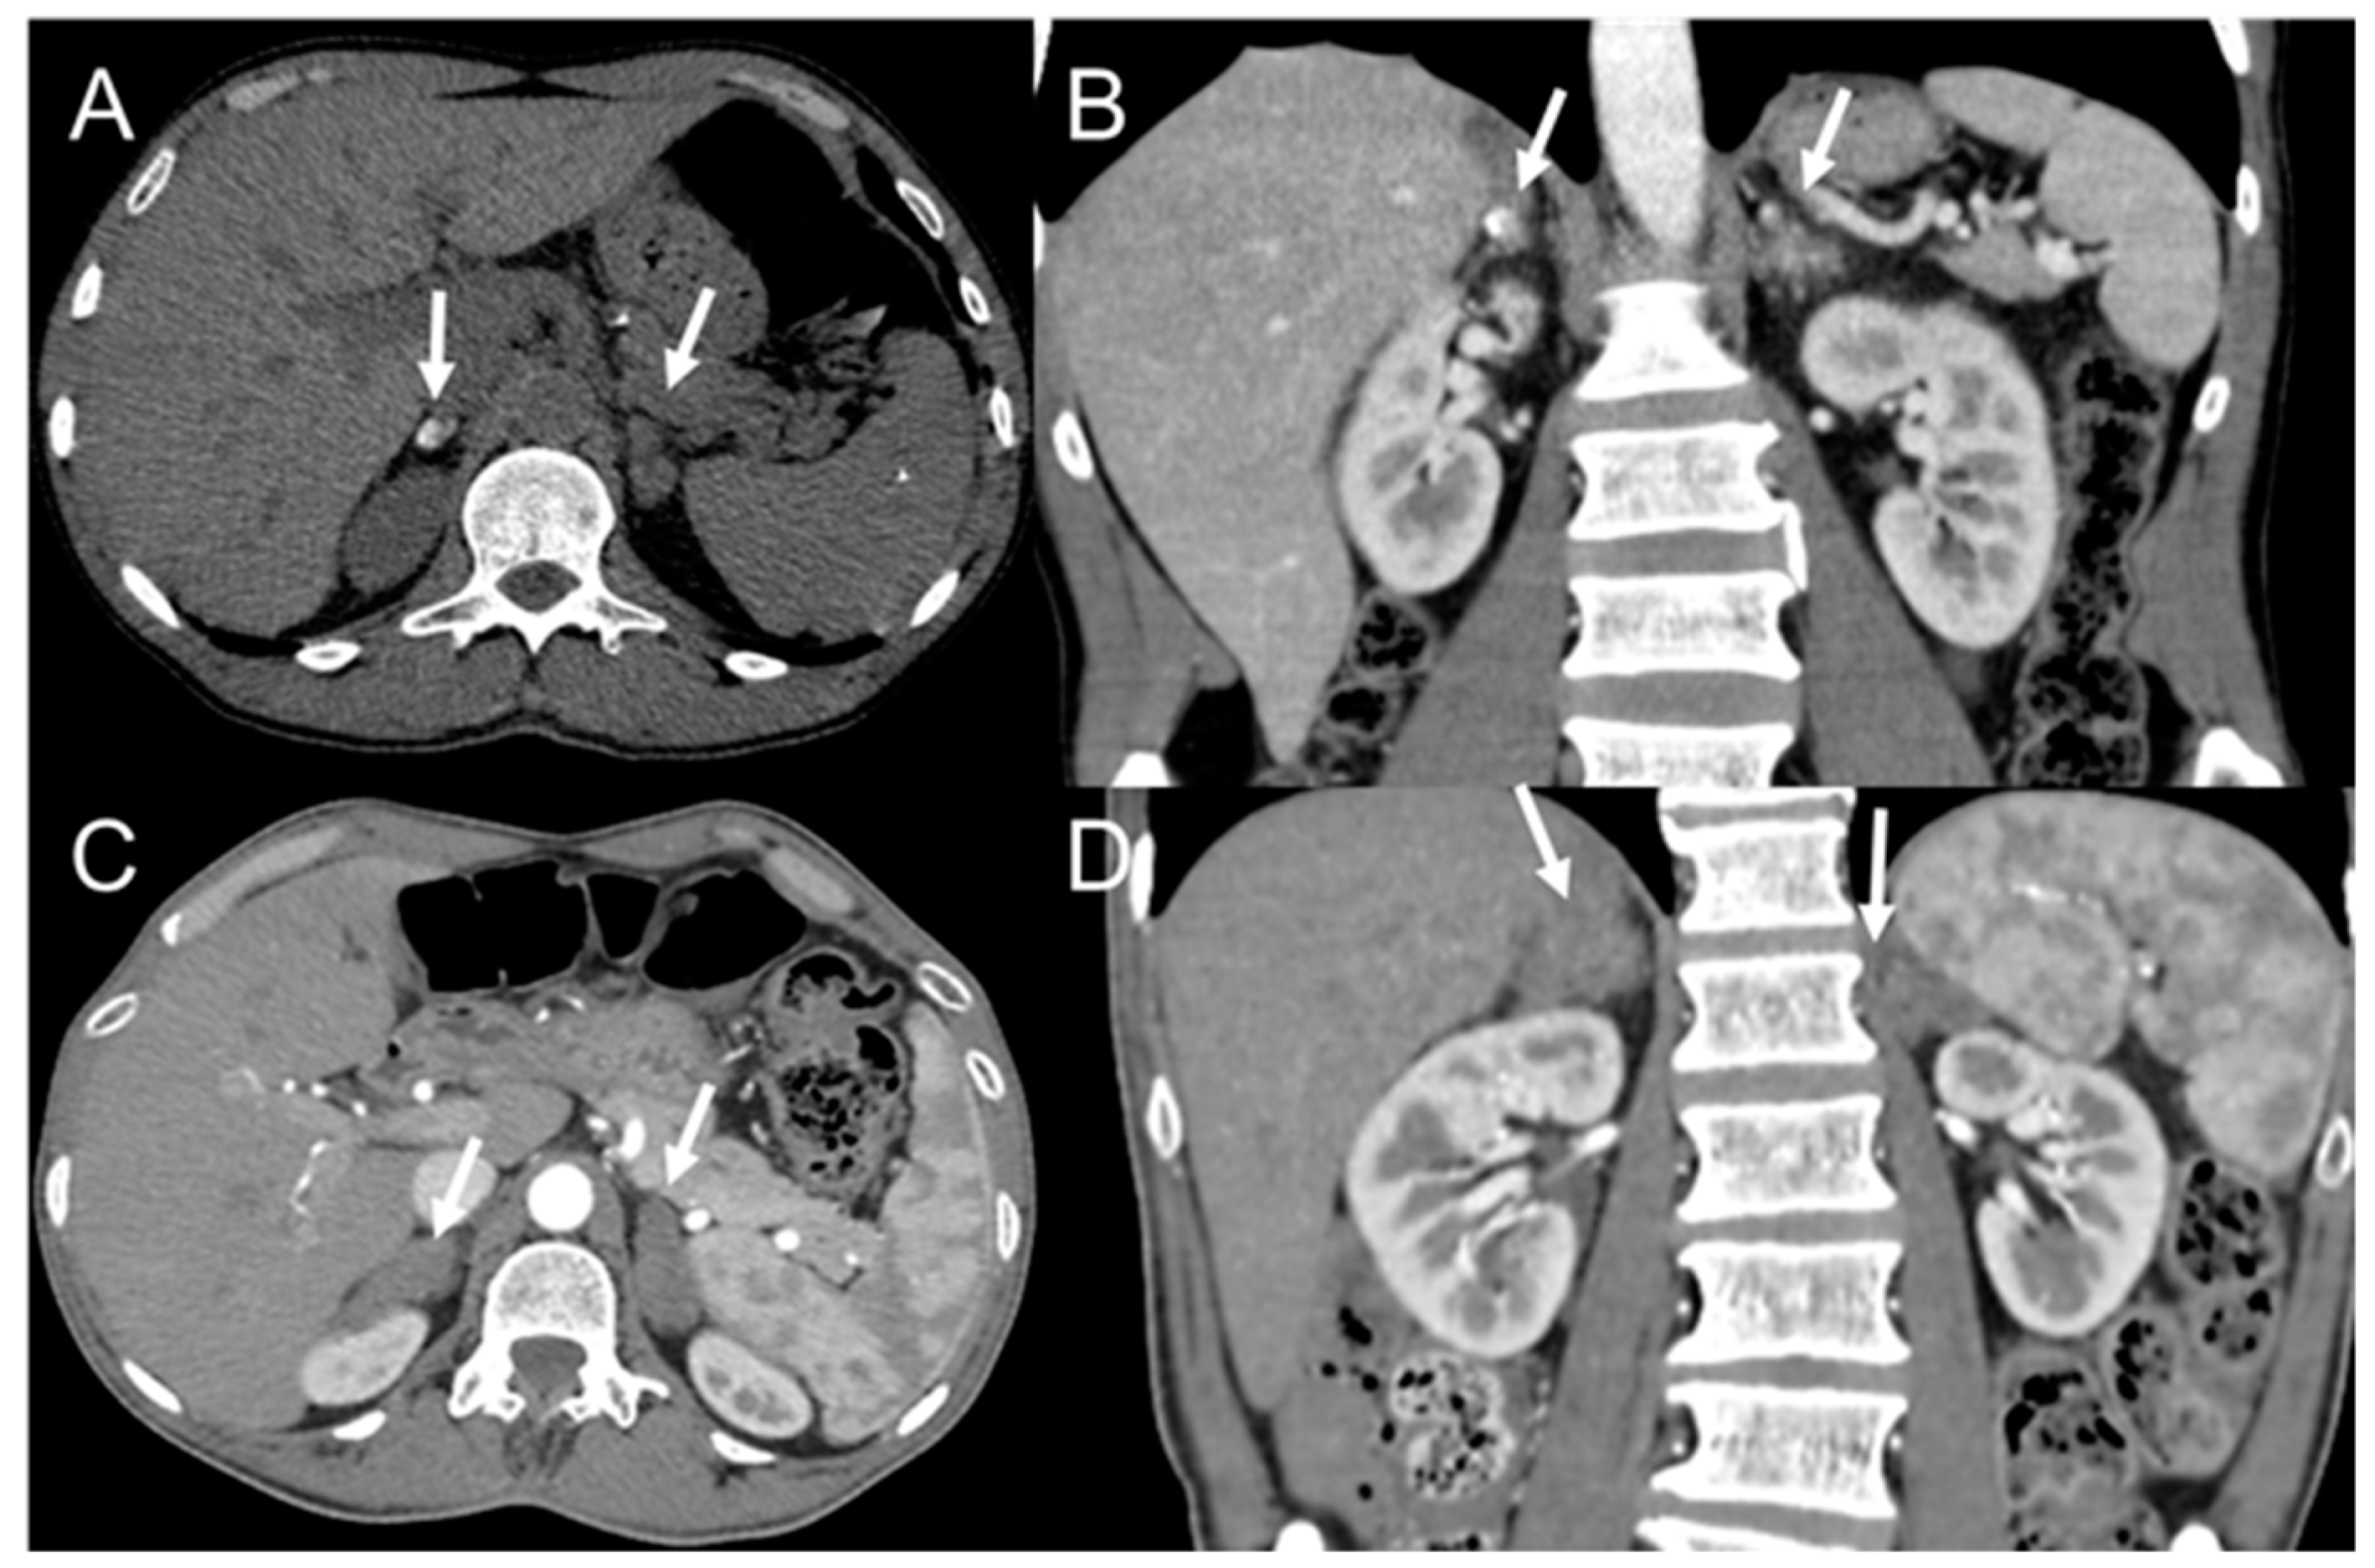

- Rosa Junior, M.; Baldon, I.V.; Amorim, A.F.C.; Fonseca, A.P.A.; Volpato, R.; Lourenco, R.B.; Baptista, R.M.; de Mello, R.A.F.; Pecanha, P.; Falqueto, A. Imaging paracoccidioidomycosis: A pictorial review from head to toe. Eur. J. Radiol. 2018, 103, 147–162. [Google Scholar] [CrossRef]

- Vermelho, M.B.; Correia, A.S.; Michailowsky, T.C.; Suzart, E.K.; Ibanes, A.S.; Almeida, L.A.; Khoury, Z.; Barba, M.F. Abdominal alterations in disseminated paracoccidioidomycosis: Computed tomography findings. Radiol. Bras. 2015, 48, 81–85. [Google Scholar] [CrossRef][Green Version]